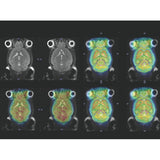

The PET Inserts for simultaneous PET/MR imaging of mice and rats provides unique insights into molecular and functional processes, by combining the highest PET sensitivity with multi-parametric MRI imaging

The PET inserts are designed for simultaneous PET and MR imaging of mice and rats using BioSpec MR imaging products. It allows researchers to gain unique insight on molecular and functional processes as well as a multitude of macroscopic and chemical information within a living system at the same time.

All  PET Inserts are based on the Bruker Si PET imaging platform that is designed for highest sensitivity, high spatial resolution and quantification accuracy across the entire FOV, highest count rates and full MRI compatibility without interferences between the hybrid modalities.